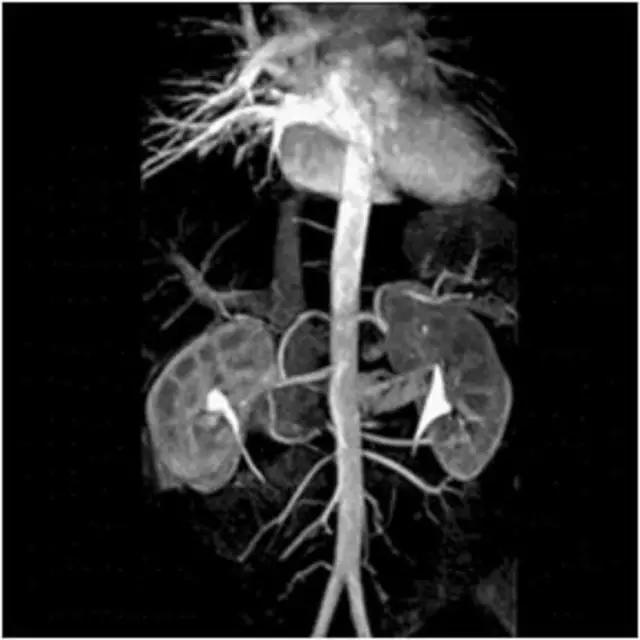

流动(空白)效应:流动液体(血液、脑脊液)不产生信号。

3、心脏大血管